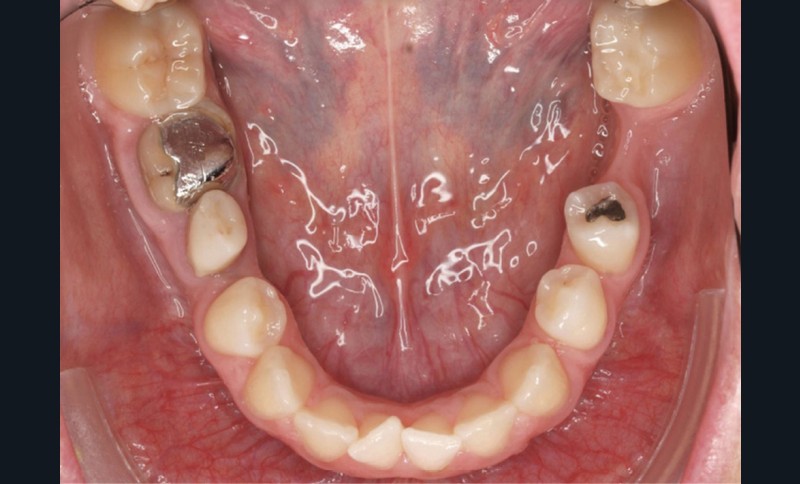

Diagnostic (fig. 1a-g)

La patiente présente une classe III squelettique dans un contexte hyperdivergent associée à une endoalvéolie maxillaire, un articulé inversé antérieur, une rétroversion incisive maxillaire, des rapports de classe I canine bilatérale, une absence de 16 et 36.

Au niveau esthétique, le profil est rectiligne. La lèvre supérieure est plus effacée, en retrait par rapport à la lèvre inférieure. De face et de profil, la mandibule paraît massive et le maxillaire effacé : le manque de soutien de la lèvre supérieure contribue à cette impression.

Le sourire est étroit, dégradé par les malpositions dentaires.

Au niveau fonctionnel, il existe un pro-glissement mandibulaire et un articulé inversé antérieur. Le profil téléradiographique montre en occlusion des rapports labiaux et un profil de classe III plus marqué que sur photographies.